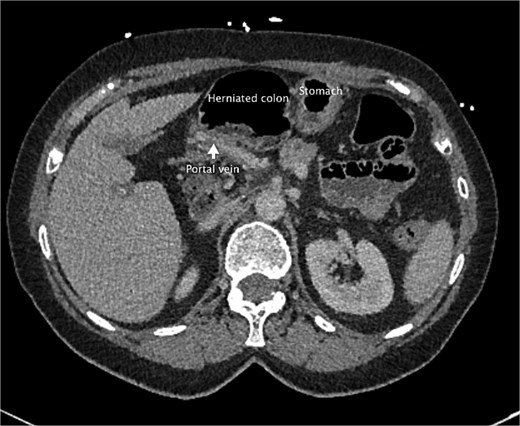

She had a computed tomography (CT) abdomen and pelvis in the emergency department, which was initially reported as mesenteric panniculitis. She had an initial lactate of 3.3 mmol/l (reference range < 2.0), other blood tests, including white cell count and hemoglobin level, were normal. C-reactive protein was also normal. She was referred to the surgical team in the morning to determine a follow-up plan as her pain had improved and she was planned to be discharged home. On review by the surgical team, she was clinically well, her abdomen was soft and not tender on examination. However, on review of the CT images, there appeared to be a dilated segment of colon in the right upper quadrant, and on further analysis, it appeared to be a Foramen of Winslow hernia containing colon. There was also an area that appeared to demonstrate a potential filling defect in the portal vein along with periportal oedema. This raised the concern of a potential thrombus versus vascular congestion (Figs 1 and 2).

An axial slice from the pre-operative CT abdomen pelvis in portal venous phase. There is an arrow pointing to narrowed appearance of portal vein. Also labeled are the herniated colon anteriorly and the stomach to the left of the herniated colon.